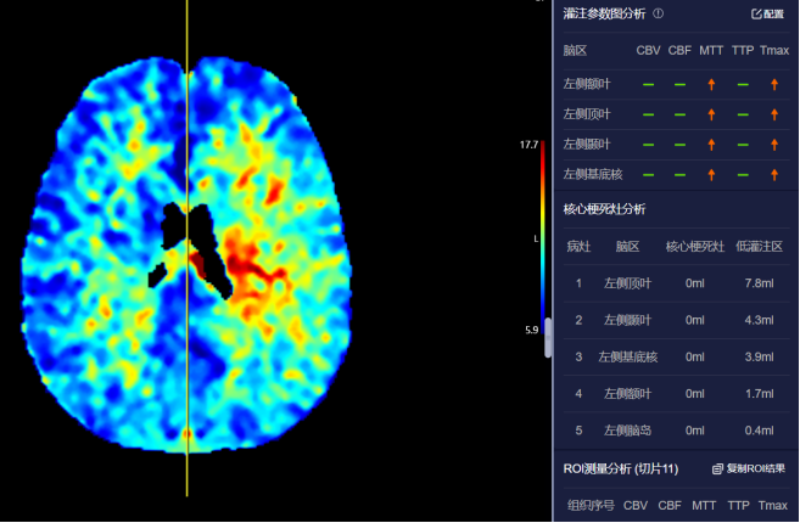

血管诊断、脑血管灌注成像

头颈部CTA、冠状动脉CTA、肺动脉CTA及肢体CTA是一种无创、低风险、快速的检查方法,能够清晰识别血管狭窄、畸形或斑块,明确病灶与周围正常组织的位置关系,为治疗方案的制定提供有力依据,能提高患者生存率,缩短高危患者急救救治时间。

以往,放射科医生进行头颈部CTA和冠状动脉CTA重建后处理,需要医生应用工作站手动处理,耗时约20-30分钟。而AI人工智能辅助诊断系统通过计算机视觉和深度学习技术,仅需5-10分钟即可完成影像重建的后处理计算,一键生成精准的三维重建图;系统还能自动标记血管名称、快速判断斑块性质,并根据最新指南对狭窄程度进行分级诊断等,帮助医生快速定位病变节段,准确分析斑块类型及狭窄程度;对脑血管灌注成像进行快速重建和诊断,大幅缩短患者等候检查和获取诊断报告的时间。